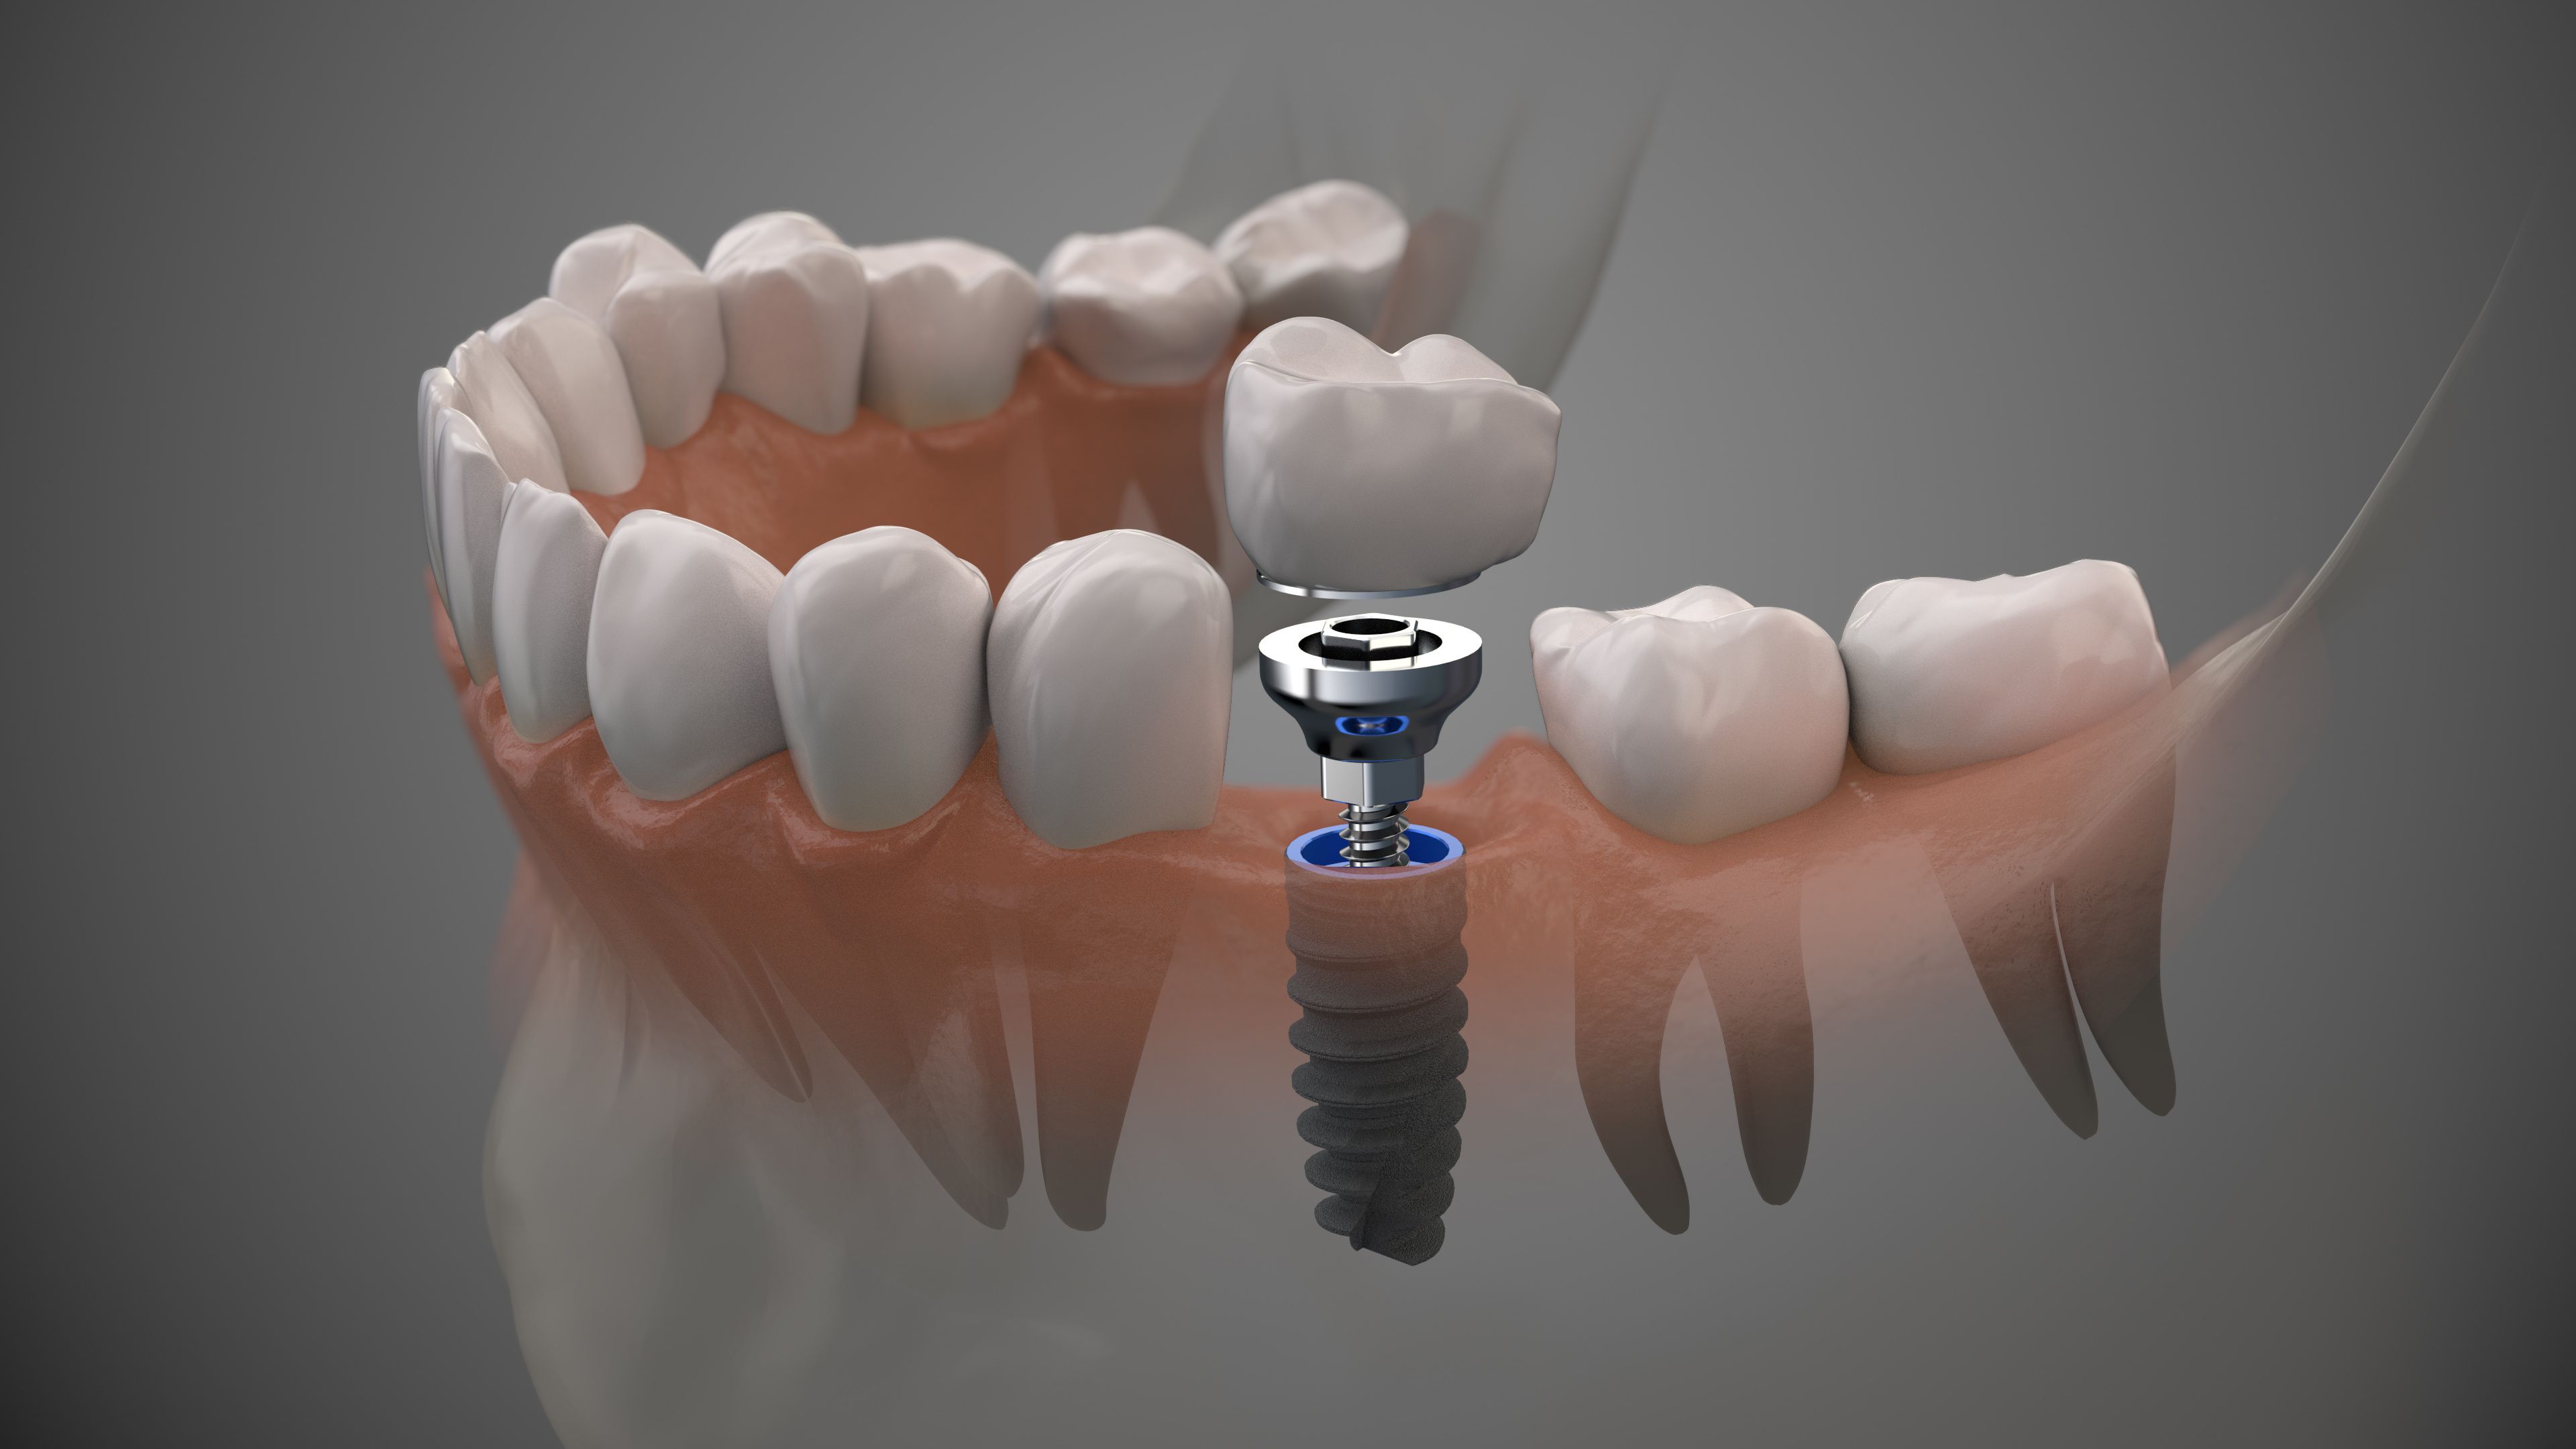

Современная стоматология: Железные зубные импланты